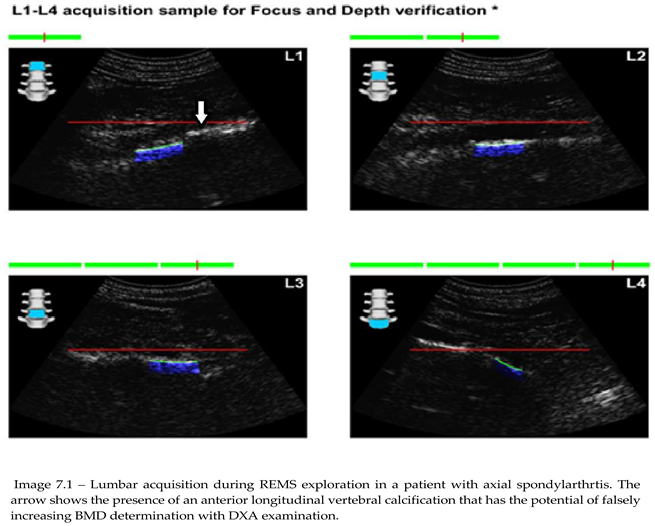

15]. Moreover, REMS recognizes extraskeletal calcifications (aortic, ligamentous, etc.), which may influence the interpretation of other imaging results [

16]. This unique feature allows REMS to provide a more accurate reflection of bone health, particularly in conditions like SpA, where axial skeleton abnormalities can complicate traditional bone density assessments.

Of the 76 patients with SpA that presented for REMS evaluation, 2 had recent vertebral fracture, one classified as grade I wedge modification on the Genant scale affecting T8 vertebra. Imagistics done during clinical practice for these patients didn’t show any structural modification related to AxSpA. The other patient had a grade I crush deformity on L4 vertebra, X-ray showing multiple syndesmophytes in the lumbar area (Image 9.1).

The results further confirm the scientific literature data that underscores the risk of osteoporosis in patients with SpA. Furthermore, a statistical analysis comparing DXA and REMS techniques has shown that REMS has a slightly higher sensibility in detecting bone demineralization in patients with chronic axial involvement, making this a reliable tool for clinical use, also given its lower financial stress on public health systems. This opens up the possibility of monitoring either osteoporotic-specific treatments or DMARD treatments in specific inflammatory rheumatic diseases of the spondylarthritides group. These results might primarily stem from the ability of the method to discern between bone and other calcifications related to a multitude of pathologies. Moreover, although both methods offer results in 2D (g/cm2), the flexibility in examining vertebral sites by angulation of the transducer and orienting ultrasound waves towards the area of interest may provide options for avoiding large calcifications or other artifact-generating conditions. Thorough preparation is needed to do REMS on the lumbar spine since improper dietary habits might lead to excessive gas accumulation in the bowels that act as an ultrasonic shield, dispersing sound waves and invalidating the examination.